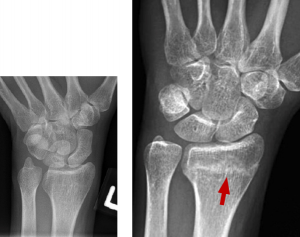

BELOW: Day 1 – normal

RIGHT: Week 4 – sclerosis across distal radius